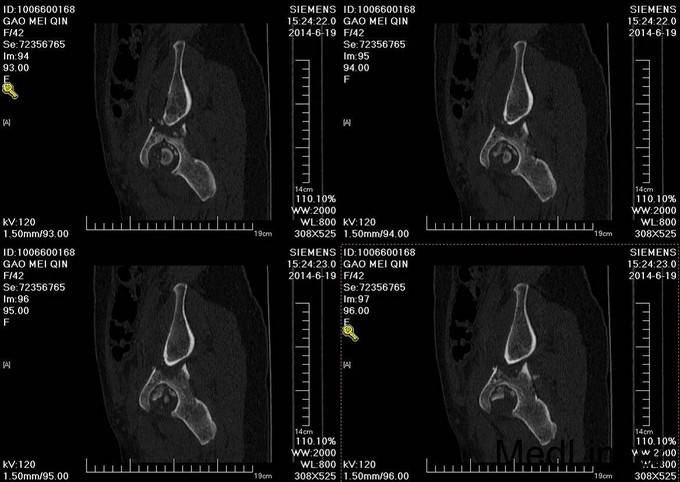

主诉:车祸外伤后左髋部疼痛伴活动受限4天 患者于2014年6月12日早6点左右被皮卡车撞伤,伤后患者出现一过性昏迷,被急诊送往当地医院,行DR及CT检查后,诊断为:左髋臼骨折,于当地医院骨科行骨牵引、抗炎补液等对症治疗后,现为求进一步治疗转入我科,患者病来无头晕头痛,无恶心呕吐,已排气排便.

患者左下肢股骨髁上骨牵引中,左髋部肿胀,臀部可见淤血瘀斑,骨盆分离挤压试验(+),左大腿肿胀,左下肢无明显短缩,纵向叩击痛(+),左下肢小腿外侧及足背麻木感,足背伸肌力正常,双足趾可活动,双侧足背动脉可触及搏动

入院后请神经外科会诊,请麻醉科会诊评估手术风险,查无明显手术禁忌症后,全麻下行左髋臼骨折切开复位内内固定术,术后留置引流,术后3天拔除引流管,切口换药无红肿渗出,术后4天转入当地医院继续治疗。